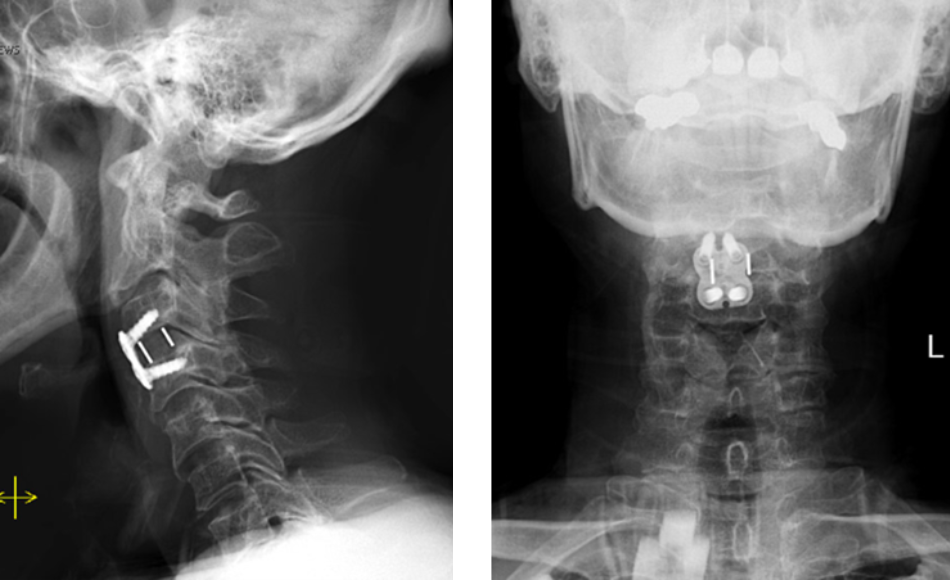

Figure 2. Lateral and AP cervical spine x-rays s/p ACDF